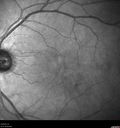

70 year old female diagnosed with diabetes 2 years ago. Her blood pressure was normal at 116/73. She has vision loss for 6 months in both eyes. VA is 20/100 OU. OCT-A shows macular ischemia.

Diabetic Macular Ischemia - Enlarged FAZ - OCT-A432 views70 year old female diagnosed with diabetes 2 years ago. Her blood pressure was normal at 116/73. She has vision loss for 6 months in both eyes. VA is 20/100 OU. OCT-A shows macular ischemia.00000